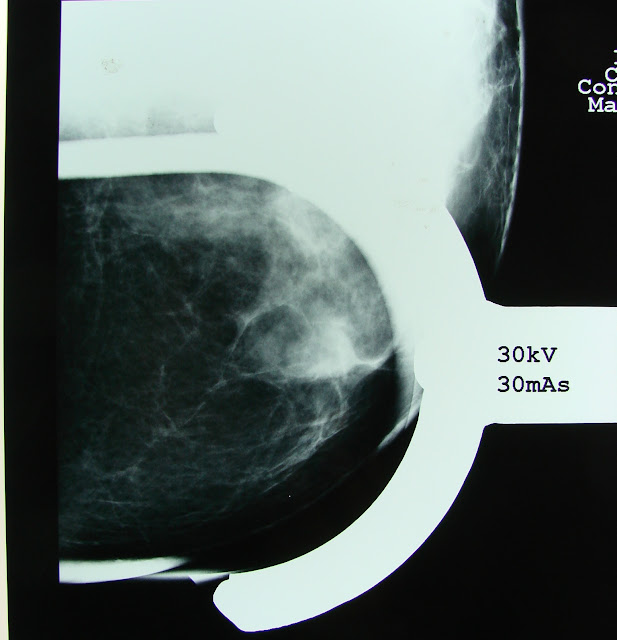

2009 after 2 years in control , conventional image studies were performed :

Remaining Breast Mammogram Lateral Oblique View : dense breast tissue in her inferior quadrants , superior isolated density with a "linear" aspect. |

Cefalo Caudal view : persistance of the density in th upper and now external quadrant . And internally an ovoidal density

| Close up for the superior density. No calcifications were seen. |

Magnification of the upper and external density ,

compatible with a linear " scar "image no

calcifications were delineated either. .

Magnification of the internal lesion , opaque and ovoidal

Magnification of the internal lesion , opaque and ovoidal